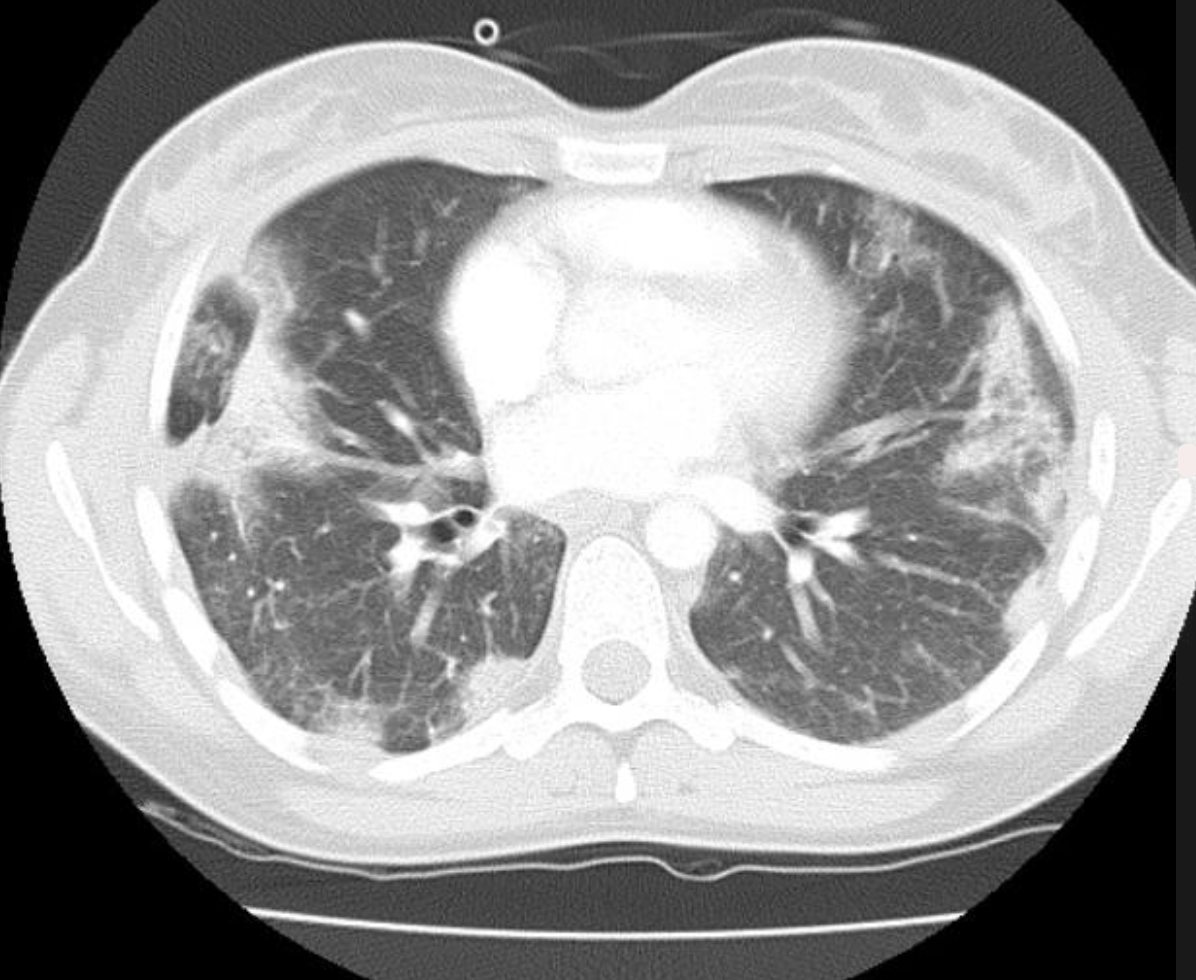

Cryptogenic Organising Pneumonia

• ALSO KNOWN AS

• bronchiolits obliterans organising pneumonia (BOOP)

• HRCT findings

• Patchy consolidation/GGO

• Subpleural, peribronchial

• Lower lung > upper

• +/- centrilobular nodules

• +/- large irregularly shaped masses

• ATTOL sign (1st picture) crescent shaped opacity

• REVERSE HALO sign (second picture)

• central GGO with surrouding consolidation.